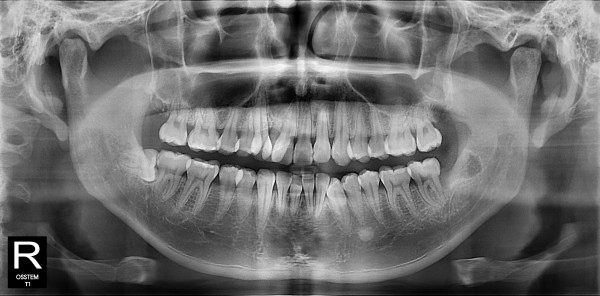

사랑니발치 20대/남성

5e20e086184bc11a2d853605b7813944_1764319844_3947.jpg